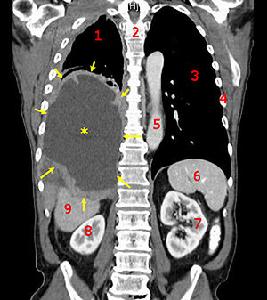

3.實驗室檢查B超和CT檢查,可發現薄片狀腫物圖象和腹水。腹水為滲出液,也可為血性。腹水中透明質酸如增高至120ug/ml,對診斷很有幫助。腹水中找到新生物性間皮瘤細胞具有診斷價值,也可對腹水中間皮細胞染色體進行分析,有助於診斷。腹腔鏡檢可見腹膜表面滿布結節和斑塊,活檢病理檢查可證實診斷。需注意與結核性腹膜炎、腹膜轉移瘤相鑑別。

腹膜間皮瘤對主訴慢性腹痛、腹脹的中、老年病人,特別是有腹水和(或)腹塊者,經超聲或CT檢查證實腹腔內腫塊或腹膜上有結節;腹水呈滲出性,腹水透明質酸顯著增高;血清CA125上升,應高度懷疑PMM。對這些患者應予以超聲或CT引導下穿刺活檢,腹腔鏡檢查,甚至剖腹探查;在估計腫瘤擴散範圍的同時,於髒層和壁層腹膜多處活檢,取得足夠組織,供病理檢查和組織免疫或化學檢查。多數PMM患者在確診時,已難以手術完全切除腫瘤。如無腸梗阻表現,應先給予2~3個療程誘導性腹腔內化療,以最大限度地減少腫瘤在腸管表面種植,為外科手術創造條件,並有助臨床醫生掌握腫瘤對化療反應的資料。在誘導性化療後2個月,施行減瘤手術,切除病變腹膜,力求清除所有腫瘤組織。術中或術後早期應給輔助性腹腔內化療,並配合放療及BRM輔助治療。對術後腫瘤復發者,如條件許可應考慮再手術。